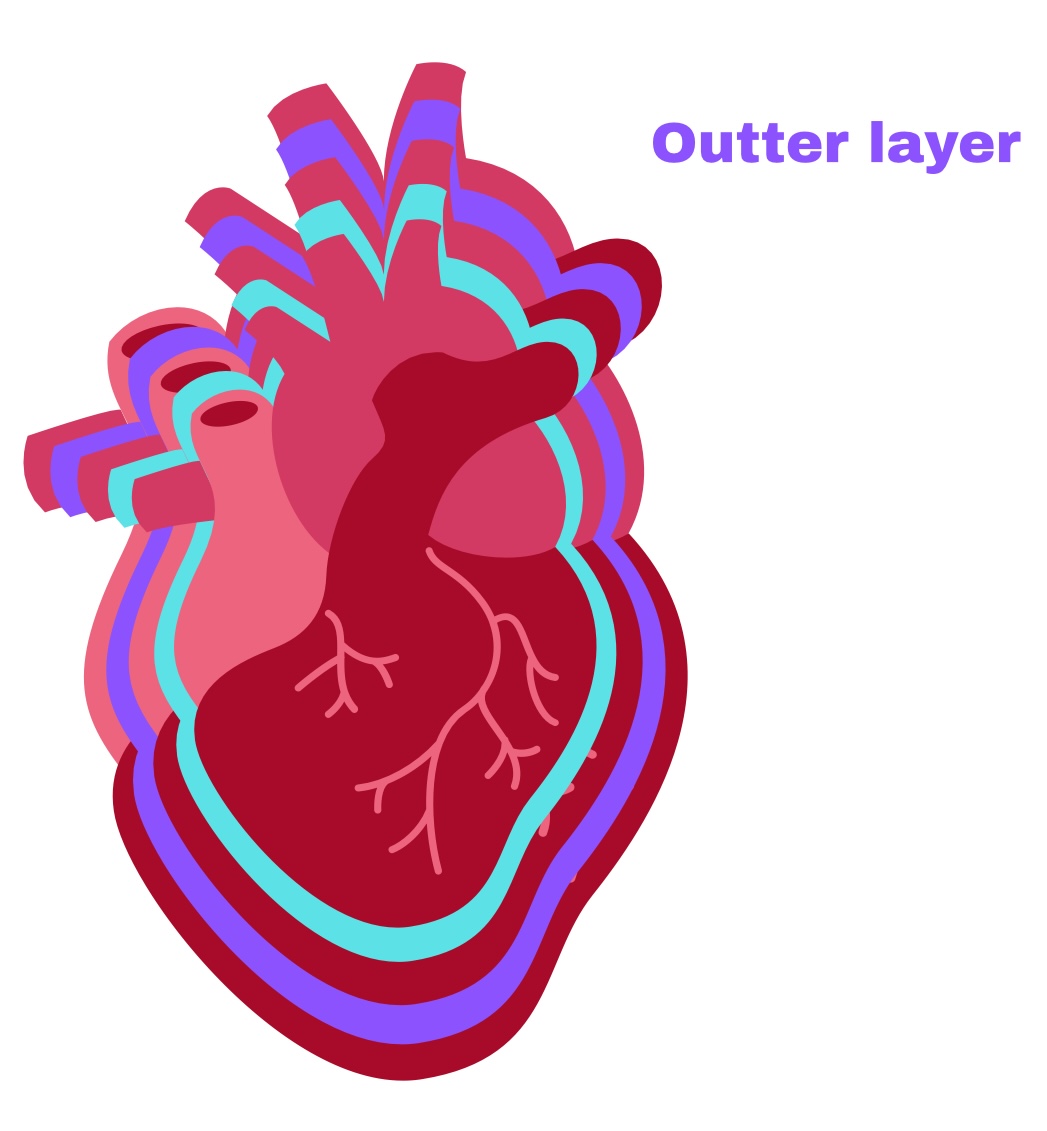

Partial Pericardium

Outer layer